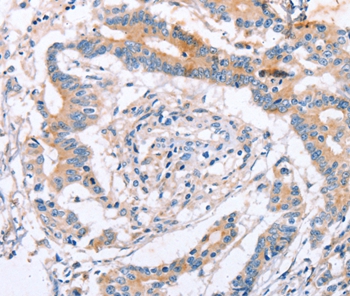

分类: 科研抗体货号: P42784别名: OGC; SLC20A4应用: WB,IHC反应种属: Human